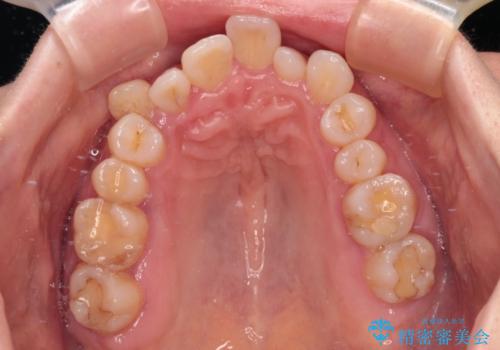

骨格的なズレを歯列矯正でカバー ワイヤー装置での非抜歯矯正

- 前歯のデコボコと咬み合わせの悪さを気にして来院された患者様です。

下顎骨が左側にズレて成長してしまったため、左側の咬み合わせが上下反対になっている状態でした。

骨格的なズレは歯列矯正のみでは改善できず、骨切除が必要となります。

そこまでの処置は望んでいらっしゃらなかったため、歯列矯正でのカムフラージュにより咬み合わせを改善することとしました。

予想通り左側の咬み合わせの調整に苦労をしましたが、最終的には違和感のない咬み合わせを達成することができました。